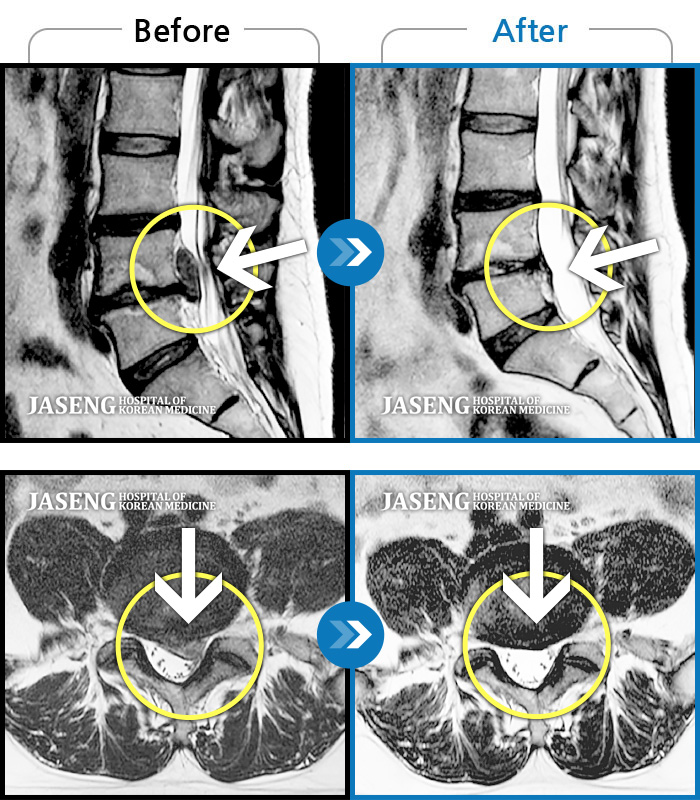

허리디스크

도움받은 사례

광주 · 이영식 원장

허리 통증과 우측 허벅지 통증 및 저림 증상 지속되어 내원하셨습니다.

촬영시기

2022.08.20 ~ 2024.11.08

2024.11.15